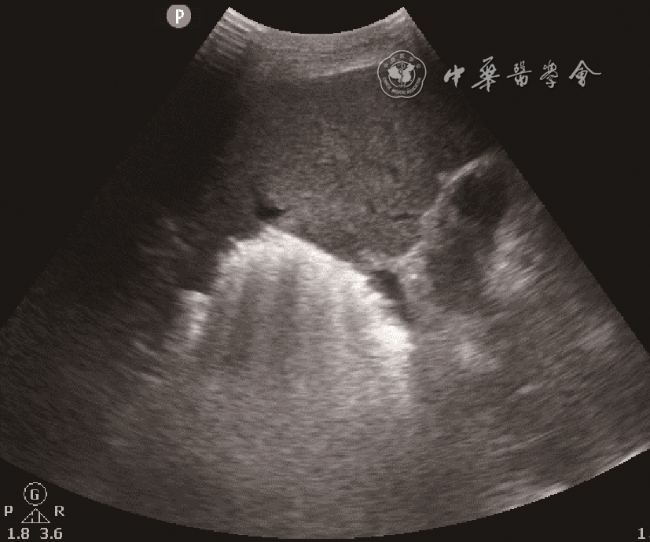

入急诊科时患者血压为60/29 mmHg(1 mmHg=0.133 kPa),心率为143次/min,末梢氧饱和度低,气管插管呼吸机辅助通气。11月26日急诊床旁超声检查提示:肝内多发高回声包块并肝静脉内气体样强回声漂动入下腔静脉、右心,肺动脉内可见大量气体样强回声,考虑产气型肝脓肿破裂(图12动态图1)。急诊平扫CT检查提示:肝多发类圆形混杂气体密度灶,肝内外胆管扩张、积气(图3)。当日血培养检出高黏性肺炎克雷伯菌(Klebsiella pneumoniae,KP),菌拉丝阳性,毒理强。血常规检查结果如下:快速C反应蛋白:243.18 mg/L(正常值范围≤10.00 mg/L);白细胞:15.93×109/L[正常值范围(3.50~9.50)×109/L];中性粒细胞百分比:93.5%(正常值范围40.0%~75.0%);血糖:38.7 mmol/L(参考值3.9~6.1 mmol/L);谷草转氨酶:247 U/L(参考值15~40 U/L);碱性磷酸酶:369 U/L(参考值45~125 U/L);谷氨酰基转移酶:349 U/L(参考值10~60 U/L);血肌酐:195 μmol/L(参考值59~104 μmol/L);尿酸:772 μmol/L(参考值208~428 μmol/L);尿常规:葡萄糖(++++)(正常值:阴性);血白介素6:2887.00 pg/ml(正常值范围0.00~7.00 pg/ml)。

图1 超声声像图示肝右叶内高回声包块(肝脓肿)

临床对于脓肿自发破裂的诊断相对困难。脓肿破裂情况下患者病情往往危重,不适宜行CT检查,床旁超声检查则成为首选。产气型肝脓肿的超声表现以脓腔内片状强回声或肝内胆管系统积气多见9。Pham等10报道1例肝脓肿破裂引起气腹及腹膜炎的病例,术前超声、CT检查均未确诊,后通过剖腹探查确诊。既往报道了1例肝脓肿破裂引起肝静脉积气的患者,超声能实时、快速地观察肝静脉内气体动态变化,这为肝脓肿破裂的诊断提供了有力证据,从而为临床治疗提供更好的指导11。超声可以观察到肝静脉内气泡的有节律的与心率相关的运动,可用于区分气泡是位于门静脉系统、肝内胆管还是位于肝静脉系统12。本病例中CT检查同样发现肝内积气,但将肝静脉内积气误认为了肝内胆管积气。本病例超声显示肝静脉内大量气泡有节律地向下腔静脉内漂动,气泡再通过下腔静脉漂动至右心、肺动脉。这种表现提示血行播散,或可为KP肝脓肿的肝外血行播散,如眼内炎、中枢神经系统感染、坏死性筋膜炎等的诊断提供线索。